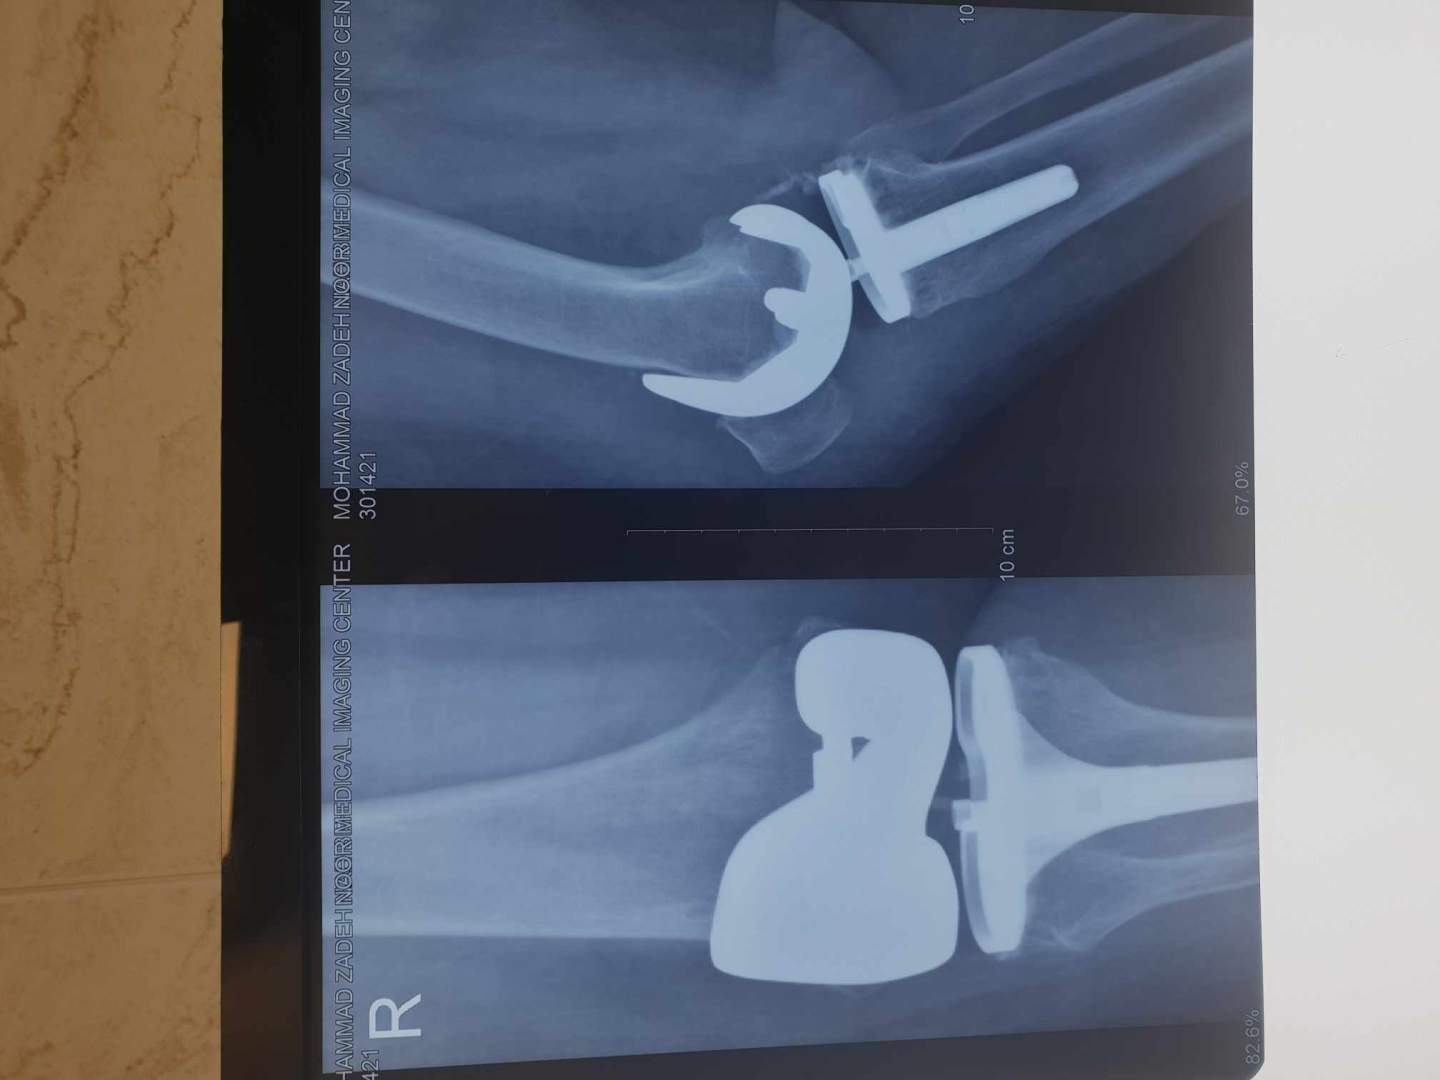

نمونه کارها

جراح و متخصص ارتوپدی